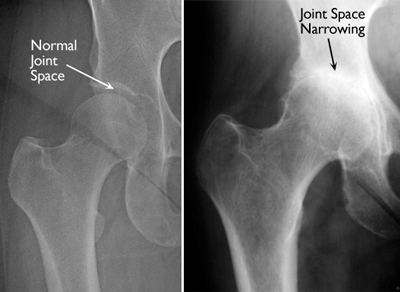

X-rays are imaging tests that create detailed pictures of dense structures, like bone. X-rays of an arthritic hip will show whether there is any thinning or erosion in the bones, any loss of joint space, or any excess fluid in the joint.

(Left) This x-ray shows a normal hip. (Right) This x-ray shows inflammatory arthritis with decreased joint space.

Reproduced with permission from JF Sarwak, ed: Essentials of Musculoskeletal Care, ed. 4. Rosemont, IL, American Academy of Orthopaedic Surgeons, 2010.